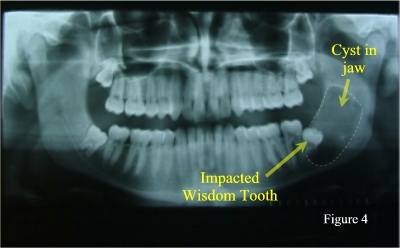

Finally, in rare cases, an impacted wisdom tooth can develop a dental cyst or dental tumour around itself (figure 4).

Cyst Associated with Impacted Wisdom Tooth